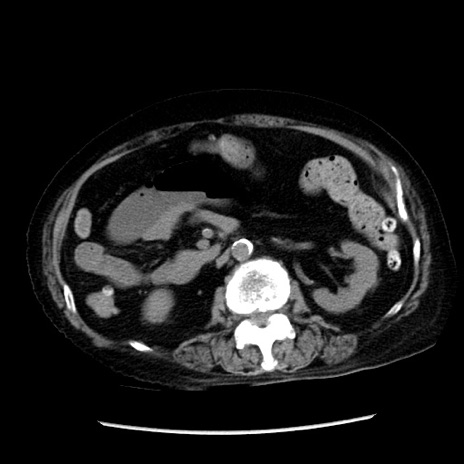

症例14(横断像)

【症例】 90歳代女性

【主訴】 腹痛・嘔吐

【現病歴】今朝から左側腹部痛を認めた。 経過観察していたが、嘔吐を認めたため来院。

【既往歴】 子宮癌術後

【身体所見】 意識清明、BP 127/54mmHg、P 98bpm Sp02 95%(RA)、BT 35.8°C、腹部平坦・軟腸ぜん動音聴取良好、右下腹部圧痛(+) 反跳痛なし

【データ】WBC 9800、CRP 0.46